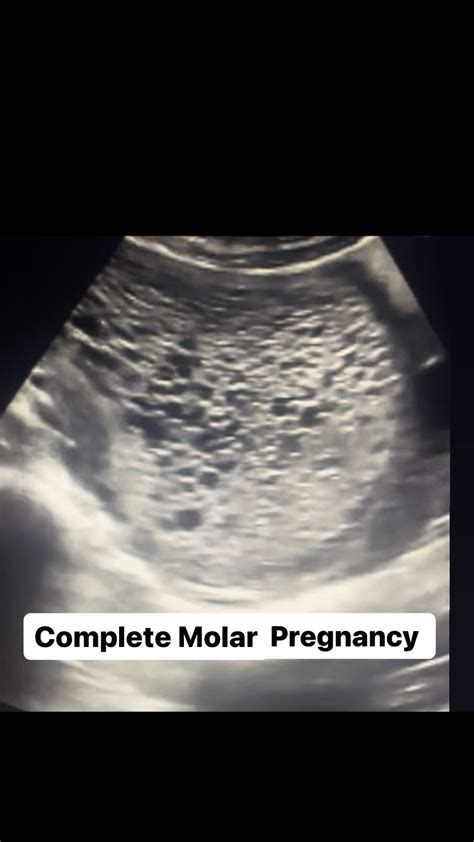

• Complete Molar Pregnancy: There is no embryo or normal placental tissue. The placental tissue is abnormal and swollen, forming fluid-filled cysts.

Radiologists look for specific visual markers to identify this condition. The most classic description of a molar pregnancy ultrasound image is often called the "snowstorm" appearance. This occurs because the abnormal placental tissue creates multiple echo-producing interfaces, making the interior of the uterus look like a blizzard on the screen.

• Absence of Fetal Parts: In a complete mole, there is an absolute lack of fetal tissue.

• Cystic Spaces: Large, fluid-filled cysts are often visible within the mass.